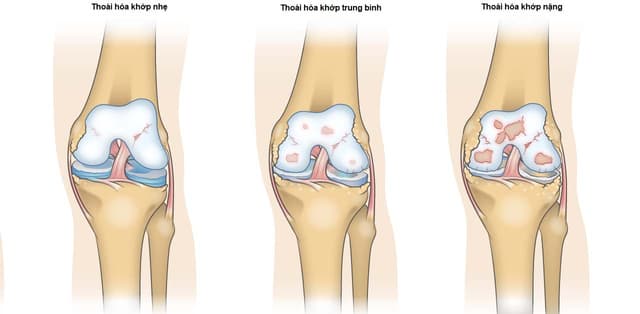

Bệnh viêm khớp mạn tính nguyên nhân và cách phòng

Bệnh viêm khớp mạn tính là bệnh xảy ra cùng với quá trình lão hóa của cơ thể.  Hầu hết các khớp chịu lực lớn của cơ thể đều bị ảnh hưởng của bệnh viêm khớp mạn tính. Bài viết dưới đây đề cập đến nguyên nhân và cách phòng bệnh viêm khớp mạn tính. Nguyên […]